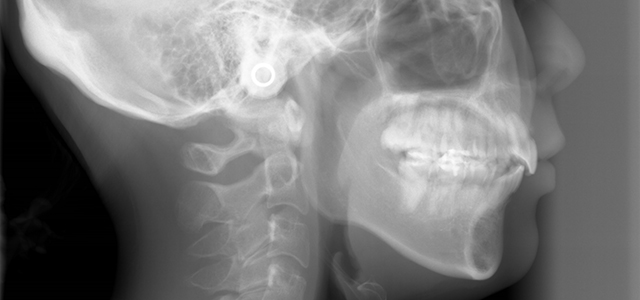

矯正前 側面セファロ

矯正後 側面セファロ